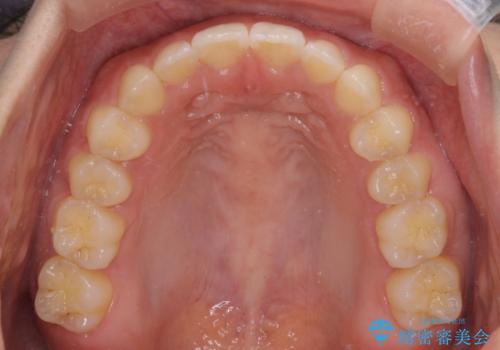

- 後戻りによる上下前歯の隙間を気にして来院された患者様です。

歯列不正はそれほど大きくなかったため、インビザライン・ライトを用いて矯正治療を行うこととしました。

無理のないペースで治療を進め、9ヶ月で終えることができました。